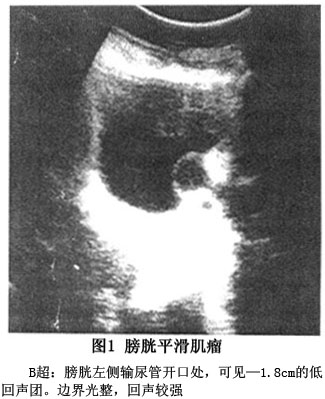

B超检查可判定肿瘤的大小、部位和范围,对诊断膀胱平滑肌瘤是最经济、实用的检查方法,可经腹或直肠进行,通常表现为低回声肿块,肿瘤表面膀胱黏膜为强回声(图1)。CT表现为膀胱壁的实质性肿瘤,CT值在30 Hu左右,肿瘤较大时可见肿瘤中心有坏死区。MRI可通过横断面、冠状面和矢状面扫描确定肿瘤的大小、部位和范围,也可了解邻近脏器的情况(图2)。膀胱镜检查发现被覆正常膀胱黏膜的膀胱壁内肿块应考虑到膀胱平滑肌瘤,但当肿瘤表面黏膜形成溃疡或糜烂时,容易误诊为恶性肿瘤。